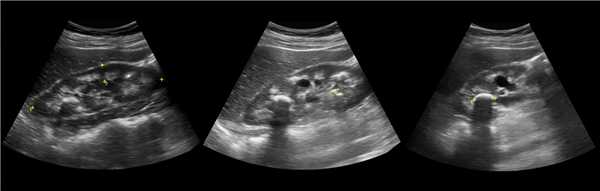

Рисунок. Дистальный отдел мочеточника расширен, в мочевом пузыре анэхогенное образование с тонким и ровным контуром — уретероцеле.

Рисунок. Двустороннее уретероцеле на УЗИ: в режиме ЦДК из верхушек уретероцеле определяется выброс мочи.

Рисунок. На УЗИ в уретероцеле определяется гиперэхогенная структура с акустической тенью — камень. Уретероцеле может являться одним из факторов, способствующих камнеообразованию.